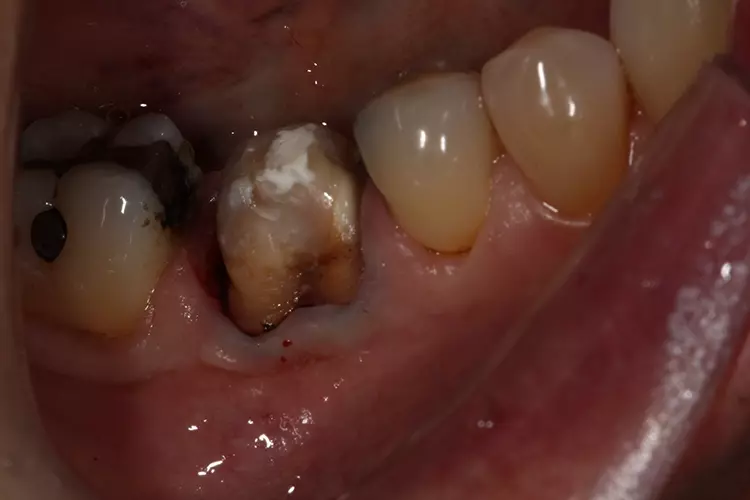

Die Behandlung begann mit dem Auftrennen und der Entfernung der Krone. Anschließend wurde die Sekundärkaries entfernt und der Stumpf mit VisCalor bulk (VOCO) repariert. Hierbei handelt es sich um ein Bulk-Fill-Komposit mit thermisch kontrollierter Viskosität, welches sich gut für Klasse-II-Restaurationen oder Stumpfrekonstruktionen eignet.

Die Krone wurde mit einem konischen Diamantschleifer mit flachem Kopf (Frank Dental) aufgetrennt. Kariöses Gewebe wurde mit einem zylindrischen Diamantbohrer (835.010C, NTI) und einem Rosenbohrer (1204025RA, Edenta) entfernt.

Die Präparation für die neue Krone erfolgte mit konischen Fräsern grober und mittlerer Körnung (850.014C/M, Solo Diamond). Nach der Kariesentfernung war eine Anhebung der tief liegenden Kavitätenränder erforderlich, die ebenso wie auch der Aufbau des restlichen Stumpfes mit VisCalor bulk (VOCO) erfolgte. Um eine Weichgewebskonditionierung zu ermöglichen, wurde eine provisorische Krone hergestellt, die der Patient vor der digitalen Abformung einige Wochen getragen hat (Abb. 2a und 2b).